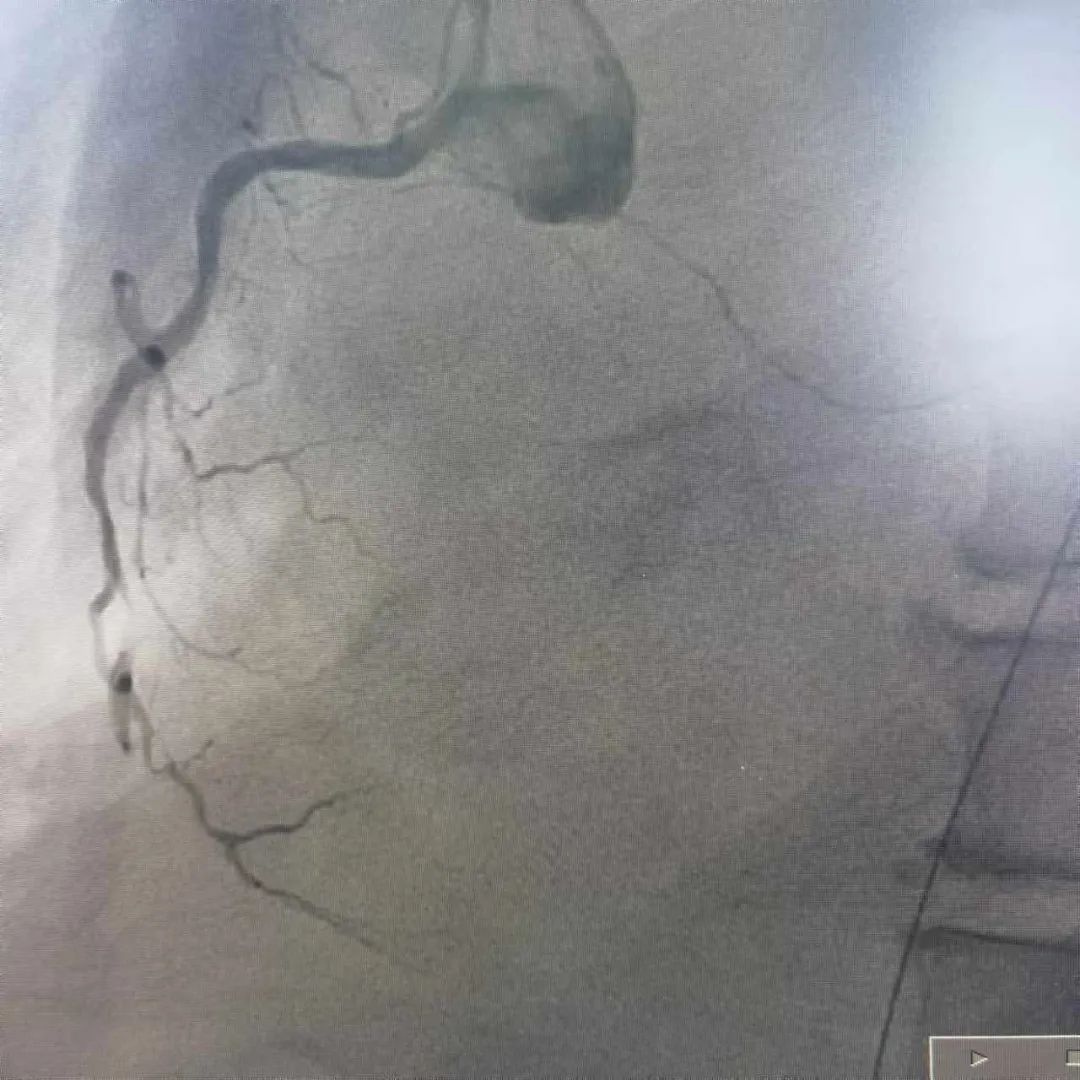

近日,玉山县黄家驷医院(玉山县人民医院)医护团队和玉山县博爱医院医护人员共同上演了一场“生命接力赛”,经过近7小时的救治,成功抢救一名呼吸心脏骤停、急性心肌梗死的重症患者。

10月17日,家住玉山县的何先生因胸闷气憋入住玉山县博爱医院,然而,在就诊过程中突发呼吸心跳骤停……医护人员立即予以心肺复苏、气管插管、电除颤等急救措施直至患者恢复自主心率,但意识仍丧失。考虑到患者病情危重,博爱医院医护团队与患者家属沟通后,即刻转至玉山县黄家驷医院(玉山县人民医院)继续救治。

发生急性心肌梗死,要采取就近抢救原则,及早送至有经皮冠状动脉介入治疗(PCI)能力的医院行PCI治疗,如就诊医院无法行PCI治疗,建议立即转至附近有PCI能力医院行PCI治疗或溶栓治疗,尽量缩短发病时间至开通闭塞血管的总缺血时间,总缺血时间越短,患者的生存率及康复率就越高。

我院胸痛中心为胸痛患者24小时开通生命“绿色通道”,早发现早诊断早治疗,能争分夺秒为患者开通闭塞血管,挽救濒死的心肌,缩小梗死的面积,保护心脏功能,及时处理心肌梗死的各种并发症,是玉山及周边地区心梗患者救治的较佳选择。

自 2021 年 4 月我院启动胸痛中心建设以来,全院上下高度重视、全员动员,有序地推进各项工作的开展,胸痛中心建设工作不断完善,于2023年8月通过国家级胸痛中心认证,成为国家级胸痛中心的一员。这标志着我院对急性心肌梗死等高危胸痛的救治水平、流程优化、硬件设施等方面均已达到国家级标准。

在推进胸痛中心建设中,我院严格做好有指征的筛查工作,就诊的病人在增加,冠脉介入术数量在增加,介入自主完成率也越来越高(急性心梗介入手术自主完成率达100%),心梗患者在本地发现率、救治率均明显提升,获得了明显的社会效益。在全市的排名中:2024上半年,急性心梗收治100例,冠脉介入手术120例,两项均位列全市第二名,仅次于上饶市人民医院,已领先于同级县医院。